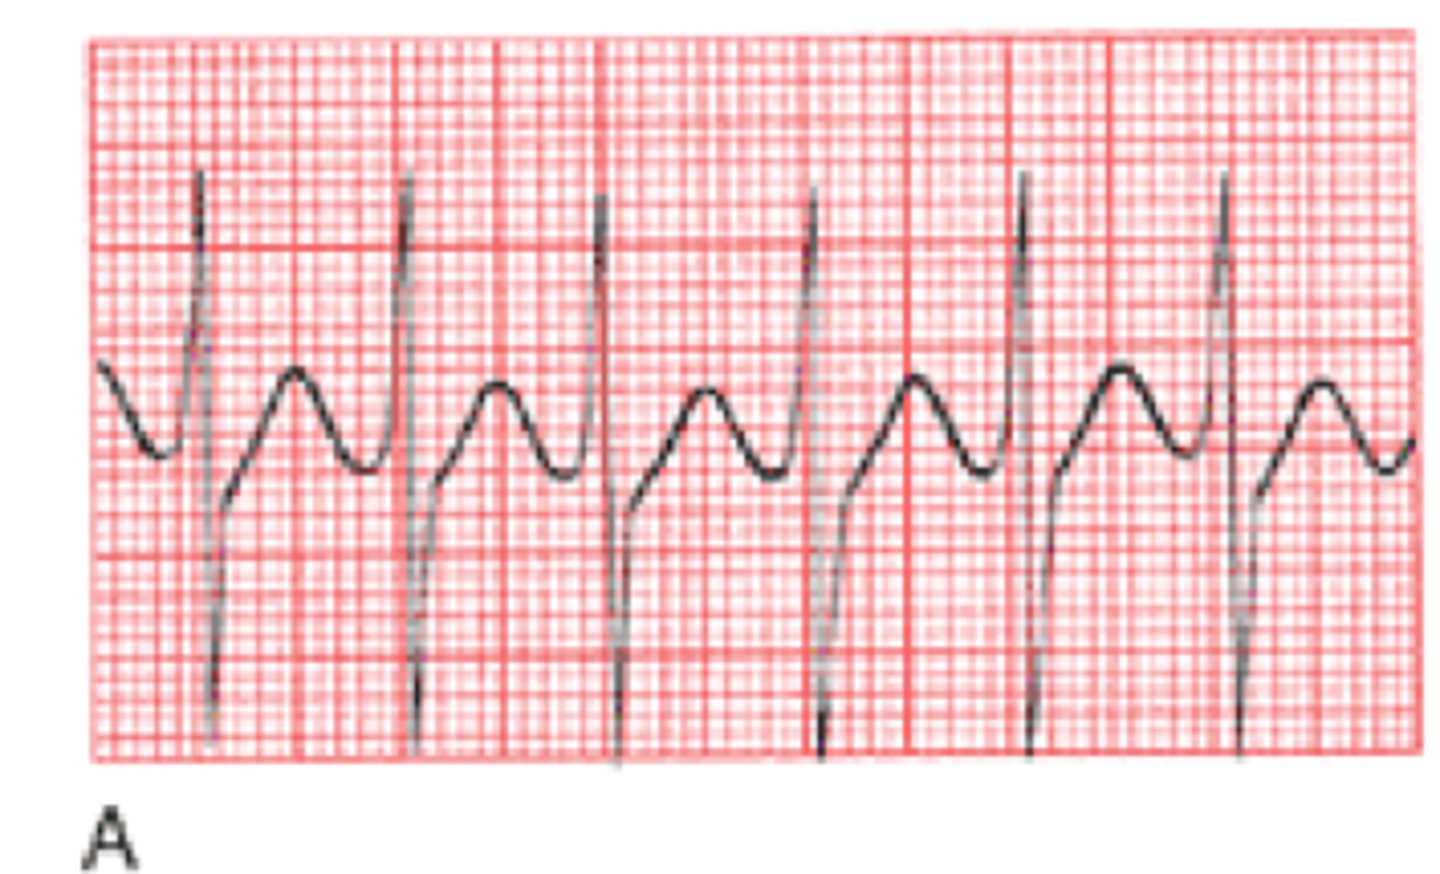

What is v tach?

BAD, ventricles are pumping too fast

What is the treatment for v tach?

Stable: O2, amiodarone, correct electrolyte imbalances

Unstable: cardioversion, O2

no pulse: defibrillate